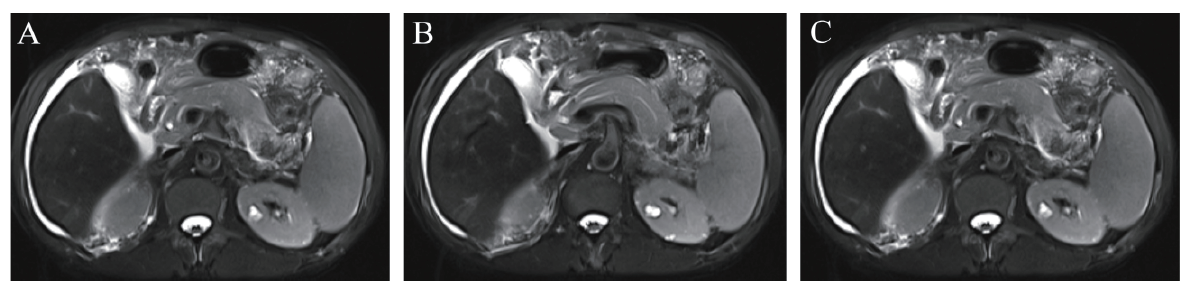

胸部CT与2022年5月16日的胸部CT比较:①双肺下叶少许炎症可能,较前新增,双肺散在纤维灶及慢性炎症,双肺肺气肿;②气管及左主支气管内少许痰栓;③双侧胸腔少量积液,较前积液稍减少。上腹部磁共振平扫+增强+磁共振胰胆管成像(图2):①肝脏强化欠均,延迟期多发小片状、结节状弱强化区,性质待定 ;②肝内少许淋巴瘀滞;③脾稍大?④胆囊炎征象;⑤腹腔少量积液,腹膜似呈小结节样改变;⑥腹腔、腹膜后多发小淋巴结显示;⑦胰腺增强扫描未见明显异常。

图2 一例PBC合并EGPA患者上腹部磁共振平扫+增强+磁共振胰胆管成像

注:A为上腹部磁共振平扫;B为上腹部磁共振增强扫描;C为磁共振胰胆管成像。

根据2022年发布的《原发性胆汁性胆管炎的诊断和治疗指南(2021)》,该患者肝功能异常排除了病毒、酒精、药物等因素,肝功能异常以ALP和GGT升高为主,免疫学指标AMA-M2 阳性,上腹部磁共振平扫及增强、磁共振胰胆管成像未见肝内外胆管梗阻,肝脏病理符合PBC表现,符合诊断标准[1]。该患者在2022年6月16日时ALP及GGT升至最高,并出现胆汁淤积,于2022年6月17日加用UDCA,经治疗后复查ALP、GGT明显下降,嗜酸性粒细胞亦随之减少,出院后随访ALP、GGT及嗜酸性粒细胞数均恢复正常。该患者肝脏病理见肝细胞少许嗜酸性病变,嗜酸性粒细胞增多可能与PBC有关。目前关于PBC合并嗜酸性粒细胞增多机制不明,国外学者观察到PBC患者嗜酸性粒细胞增多先于ALP、GGT升高,提示嗜酸性粒细胞增多可能先于肝脏病理发现,这表明嗜酸性粒细胞参与PBC疾病早期过程,而Iwashita等[2]认为PBC患者嗜酸性粒细胞增多可能与IgG4有关。